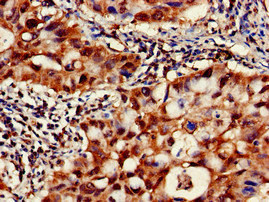

Immunohistochemistry of paraffin-embedded human lung cancer using CSB-PA004490EA01HU at dilution of 1:100